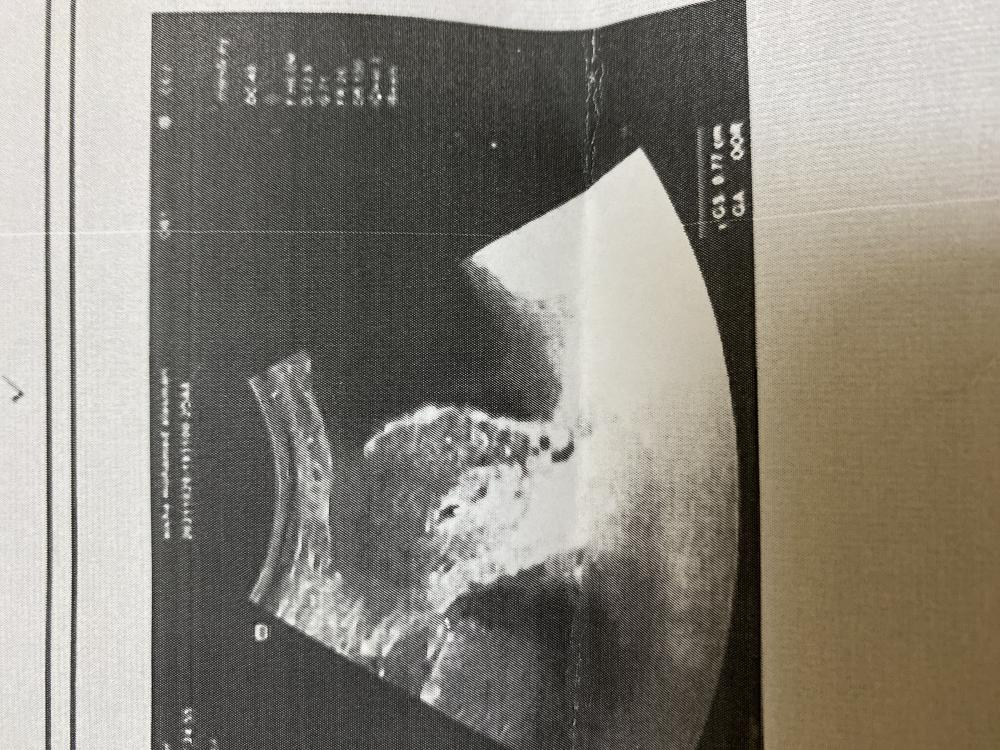

بنات شوفوا سوناري خمس اسابيع ويومين تؤام او ايش النقطتين هذي؟

السلام عليكم ورحمة الله بنات شوفوا سوناري خمس اسابيع ويومين تؤام او ايش النقطتين هذي؟

يااااارب الله يرزقك انا اشوف تووم وش قالت الدكتورره